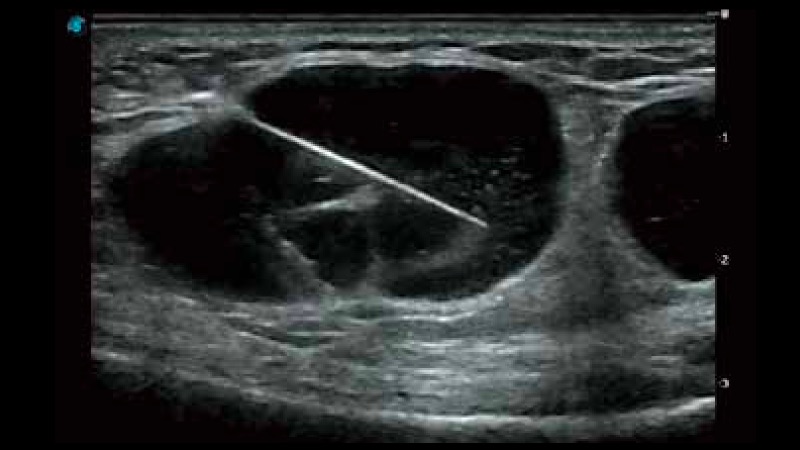

開立醫(yī)療通過不斷的技術(shù)創(chuàng)新,為大眾的生命健康提供持續(xù)關(guān)愛。P12 Plus采用全新一代超聲成像平臺(tái),新平臺(tái)旨在將真實(shí)還原組織解剖結(jié)構(gòu)作為首要目標(biāo)。平臺(tái)采用全新集成化硬件模塊,搭載新一代芯片,系統(tǒng)性能得到大幅提升,為您的診斷提供了豐富的臨床信息。優(yōu)異的圖像表現(xiàn),豐富的探頭配置,全面的應(yīng)用功能,為您日常診斷提供了可靠的助手。

P12 Plus

彩色多普勒超聲診斷系統(tǒng)